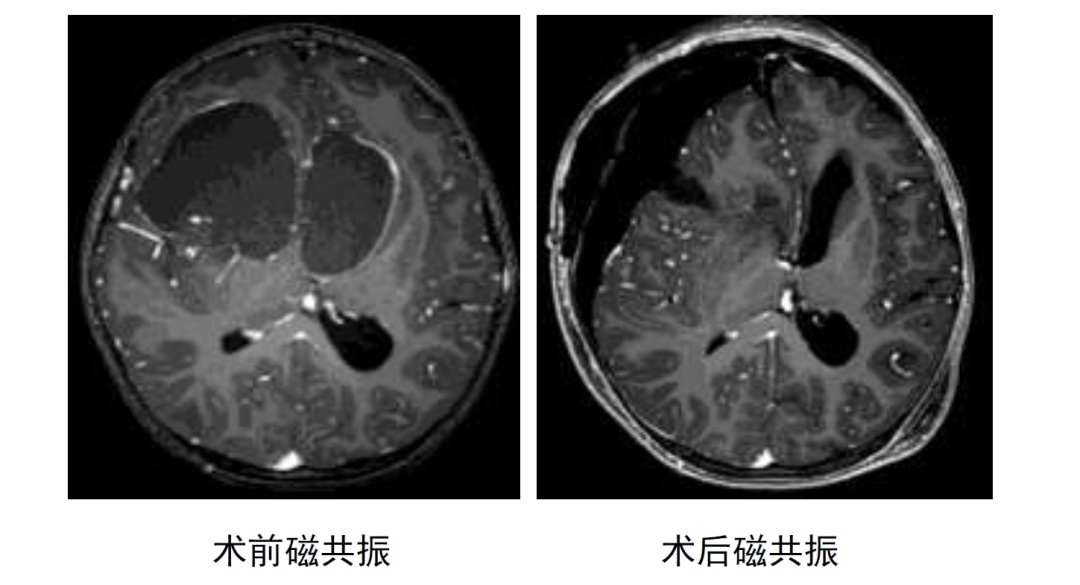

肿瘤巨大、位置特殊,手术刻不容缓!张晨冉立即将小君收入院。一系列术前检查,紧锣密鼓地进行着:头颅CT、磁共振等影像学检查,视力、视野、眼底的相关检查,及详细的体格检查。检查发现,小君右侧瞳孔扩大,对光反射消失,无光感,右眼视力完全丧失,左眼视力仍基本正常。

术中肿瘤关键部分钙化显著,包绕视神经和颈内动脉生长,且有多个大囊,如何切除实质钙化肿瘤和塌陷的囊壁,是摆在团队面前最棘手的问题。

术中可以看到右侧的视神经已经被肿瘤顶起,钙化的肿瘤包绕了右侧视神经和右侧颈内动脉,同时累及大脑前动脉。钙化的肿瘤切除起来相当困难,动脉与神经一个也动不得,这部分钙化术中几度想放弃切除,但考虑到第一次手术对小君的重要性,张晨冉凭借过人的毅力和耐心,把肿瘤缓慢从神经和血管上剥离下来。在麻醉科和护理部的顶力配合之下,经过12小时的奋战,团队全切了钙化肿瘤和肿瘤囊壁,神经和血管等结构保护完好,手术终于在翌日凌晨4点多顺利结束。

术后,在小儿重症监护室和儿神经外科医护团队的精心照料下,小君顺利度过了过山车似的电解质紊乱、垂体激素紊乱等难关,张晨冉亦是坚持每天两次查房,积极关注小君伤口、尿量、电解质及垂体功能情况。复查CT及磁共振可见肿瘤全切,没有明显神经系统受损的阳性体征。